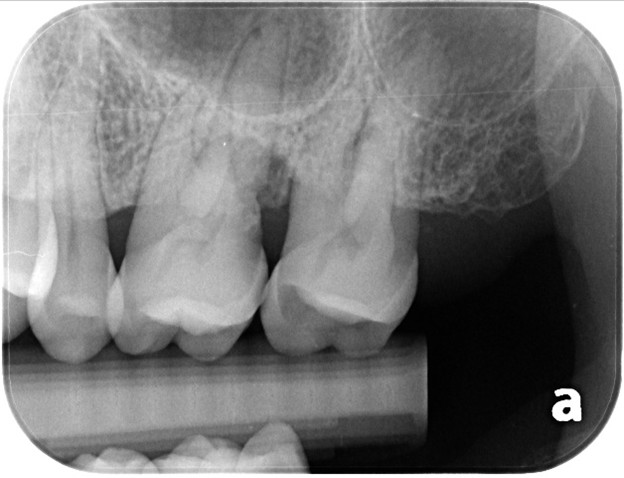

治療後的追蹤中,可以看到幾個明顯的變化:- 牙周囊袋深度:從原本約8mm,明顯改善到3mm以內(接近健康範圍)

- 牙齦狀態:牙齦變得比較緊實,顏色恢復健康的粉紅色,檢查時也不再容易流血

治療後影像